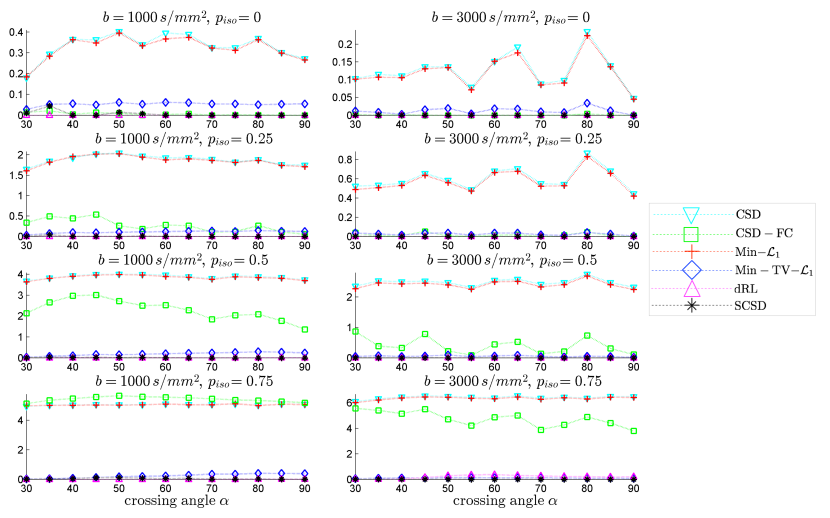

The results of our final quantitative comparison are summarized in Fig. 7, which shows the values of contrast obtained using different SD methods under comparison for s/mm2 (left column of subplots) and s/mm2 (right column of subplots). Predictably enough, the best contrast is achieved by the Min-TV- and SCSD algorithms, owing to their inherent ability to account for the presence of isotropic diffusion. Moreover, out of the two, the proposed SCSD algorithm yields the higher values of for all simulated scenarios. An additional illustration of the effect of incorporation and spatial regularization of the isotropic diffusion component is provided in Fig. 8, which depicts a 2-D “axial” slice of the IDMs reconstructed by different SD methods under comparison for s/mm2, , and . (Note that, for the sake of the clarity of visualization, the IDMs in Fig. 8 have been normalized so as to make their minimum and maximum values correspond to black and white pixel values, respectively.) One can see that the IDM reconstruction produced by SCSD is virtually indistinguishable from the original IDM (as shown in the upper, leftmost subplot of the figure), with the second best result produced by the Min-TV- algorithm. At the same time, neither CSD, Min- nor CSD-FC can attain a comparable accuracy of estimation of the spatial pattern of isotropic diffusion, as represented by the original IDM. In particular, even though their respective reconstructions do bear some global resemblance to the original IDM, the level of estimation errors is too high to deem these reconstructions useful.